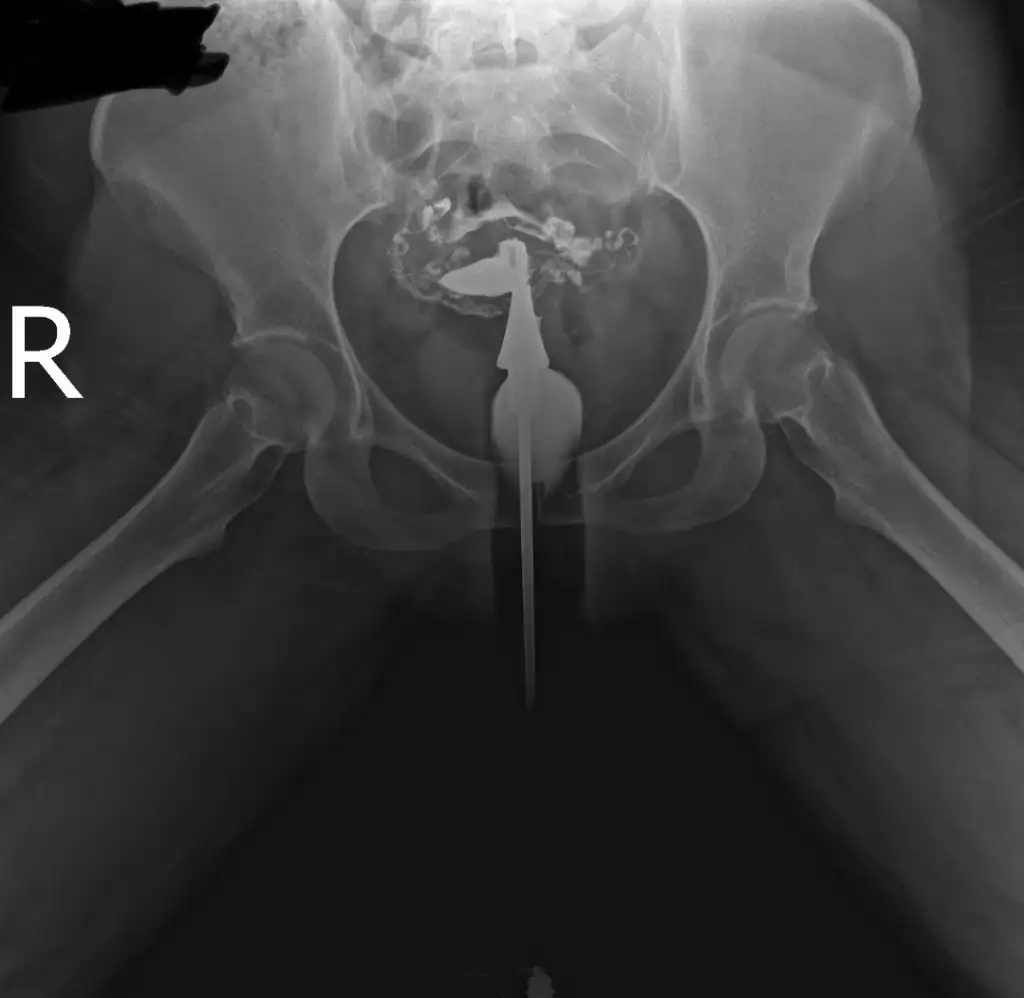

İlaç karın boşluğuna yayılmış tüplerin açık olduğu anlamına geliyor. Farklı bi görüntü var mı tek taraflı gibi duruyor gibi geldi banaHerkese merhaba bana da yardımcı olursanız çok sevinirim. Dün hsg çektirdim doktorum tüplerimin açık olduğunu söyledi. Fakat ben görüntülerden bir şey anlamadım. Bilgisi olan yorumlarsa çok sevinirim görüntüleri yüklüyorum.

Sadece bu görüntüleri yüklemişlerdi e nabıza maalesef teşekkür ederim cevabınız için şüpheye düştüm görüntüden anlamayıncaİlaç karın boşluğuna yayılmış tüplerin açık olduğu anlamına geliyor. Farklı bi görüntü var mı tek taraflı gibi duruyor gibi geldi bana

Açık dedi doktor raporda da açık yazıyordu. Benim de görüntüm böyleydi karın boşluğuna ilaç yayılmış şekildePeki sizin tüpleriniz açık mı çıktı acaba benim görüntülerden bir şey anladınız mı

Anladım teşekkür ederim bende rapor olmayınca kafam karışmıştıAçık dedi doktor raporda da açık yazıyordu. Benim de görüntüm böyleydi karın boşluğuna ilaç yayılmış şekilde

Normal görünüyor rapora göreMerhaba kızlar film sonucum bu. Bilenler bakabilir mi?